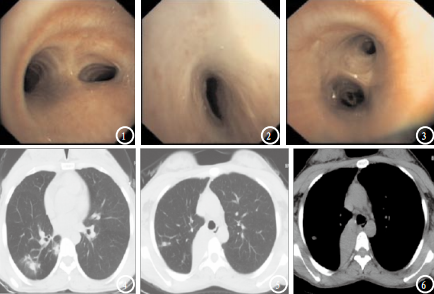

气管镜检查是通过鼻腔、口腔或气管插管进入气管和支气管以及更远端,相比于CT,可以直接观察到气管、支气管内情况,可以对看到的疾病进行干预和治疗。

那对于肺结节患者,做支气管镜大多想活检明确诊断,肺结节根据解剖位置分为中央型肺结节(纵隔和气管周围)和周围型肺结节(离胸壁较近)常规支气管镜对于周围型的肺结节,不必进行检查,因为常规支气管镜检查只能到达比较粗的支气管。

也有更先进的比如磁导航支气管镜(ENB)、超细支气管镜或支气管腔内超声(EBUS),这些新技术确实提高了周围型肺结节诊断的阳性率,但对于它的必要性和临床实用性还有待探讨,做支气管镜也有一定的限制。